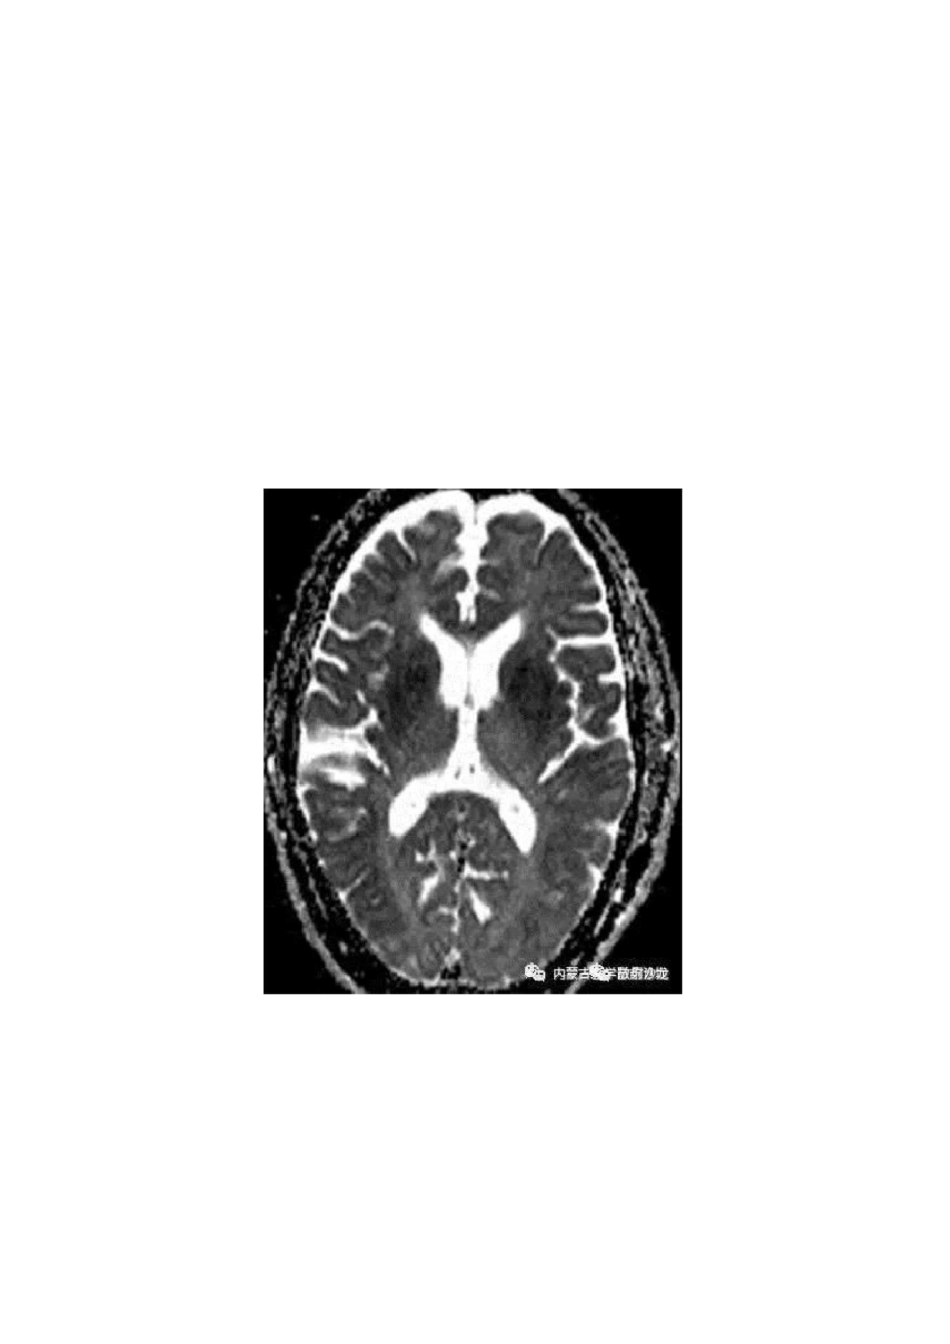

低血糖脑病的MRI表现及鉴别

低血糖脑病可发生于任何年龄,多见于中老年人,有糖尿病史和降糖药物服用史,常发生在胰岛素使用过量的患者,血糖水平低于 2.8mmol/L(50ml/dl),老年人对降糖药物,特别是磺脲类药物耐受性差。也可见于酗酒、节食减肥、饥饿、胰岛细胞瘤患者。脑组织对低血糖的耐受性是不一致的,越是进化发育程度高的组织,对缺糖的敏感性高,耐受性越差;因此,低血糖发生时首先是大脑皮层出现抑制,其次是皮层下中枢包括基底节区、下丘脑、植物神经中枢相继受影响,接下来受影响的是间脑、中脑、脑干网状结构、延脑。补充葡萄糖后按上述顺序逆转恢复。脑实质受损主要累及皮质及深部核团,受损程度取决于低血糖严重程度及持续时间。影像表现主要有下面三种情况⑻ 灰质受累为主:累及皮质、纹状体及海马等;(b) 白质受累为主:累及侧脑室周围白质、内囊及胼胝体压部;(c) 灰白质均受累。小脑和脑干是对低血糖神经损害具有较高耐受性的区域。低血糖脑病预后取决于低血糖持续时间、程度及机体状况。rj(低血糖损害中枢神经系统通常的顺序)新生儿脑代谢旺盛,低血糖脑病在婴儿中较常见,主要造成顶枕叶的不对称性损害,急性期 MRI 表现为顶枕叶皮层、皮层下斑片状长 T1WI、长 T2WI 信号,DWI 呈高信号。成年人低血糖脑病常常累及大脑皮质、胼胝体、基底节区、海马等区域,对称或不对称,病灶呈稍长T1 稍长 T2 信号,FLAIR 高信号,DWI 高信号,ADC 低信号,MRA 未见相应供血区血管病变。纠正血糖后部分病灶可逆。仅累及胼胝体者预后较好。脑干和小脑对低血糖脑损伤具有相对较高的耐受性。(DWI 对病灶显示很有意义)(M/50,既往有糖尿病和高遊病史,目前处于昏迷状态 DWI 及相对应 ADC 图片提示双侧皮质、海马回、基底节区扩散受限,且呈对称性)鉴别诊断:包括克-亚氏病(CJD)、线粒体脑肌病、皮层脑梗死、病毒性脑炎、可逆性后部脑病综合征、肾上腺危象、渗透性脱髓鞘综合征、溶血性贫血、氰化物中毒、严重脑夕 M 伤等,应结合临床病史予以鉴别。克-亚氏病:CJD 包括散发型 CJD(sCJD)、遗传型(gCJD)、医源型 CJD(iCJD)及新变异型 CJD(vCJD)。MRI 最显著的特征是大脑皮层、双侧尾状核、壳核、丘脑,在 FLAIR 序列、T2WI 呈对称稍高信号,DWI 高信号,丘脑枕部见“曲棍球征”,MRI 动态观察常能在短期内显示脑实质的进行性萎缩。线粒体脑肌病:以皮质受累为主,并呈向皮层下白质蔓延趋势,在 T2WI 呈脑回样高信号,DWI 也呈高信号,旦...